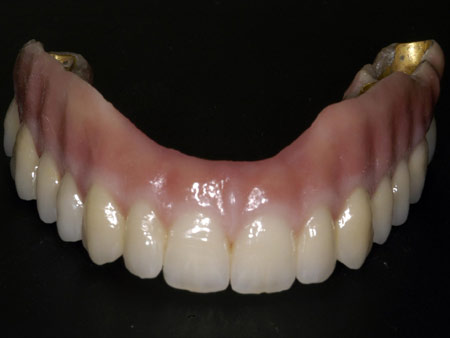

Los implantes son raíces de titanio que sustituyen a una pieza dental.Utilizamos el sistema más avanzado para colocar implantes sin necesidad de abrir la encía, con lo que disminuimos las molestias postoperatorias para el paciente, es el sistema Nobel Guide.

Así mismo existe la posibilidad de colocar una prótesis provisional el mismo día de la intervención, con lo que el paciente tiene asegurada una estética y función desde el primer día.

Otros alternativas al tratamiento: all in four, dientes en una hora, procera implant bridge, dientes de porcelana y zirconio.